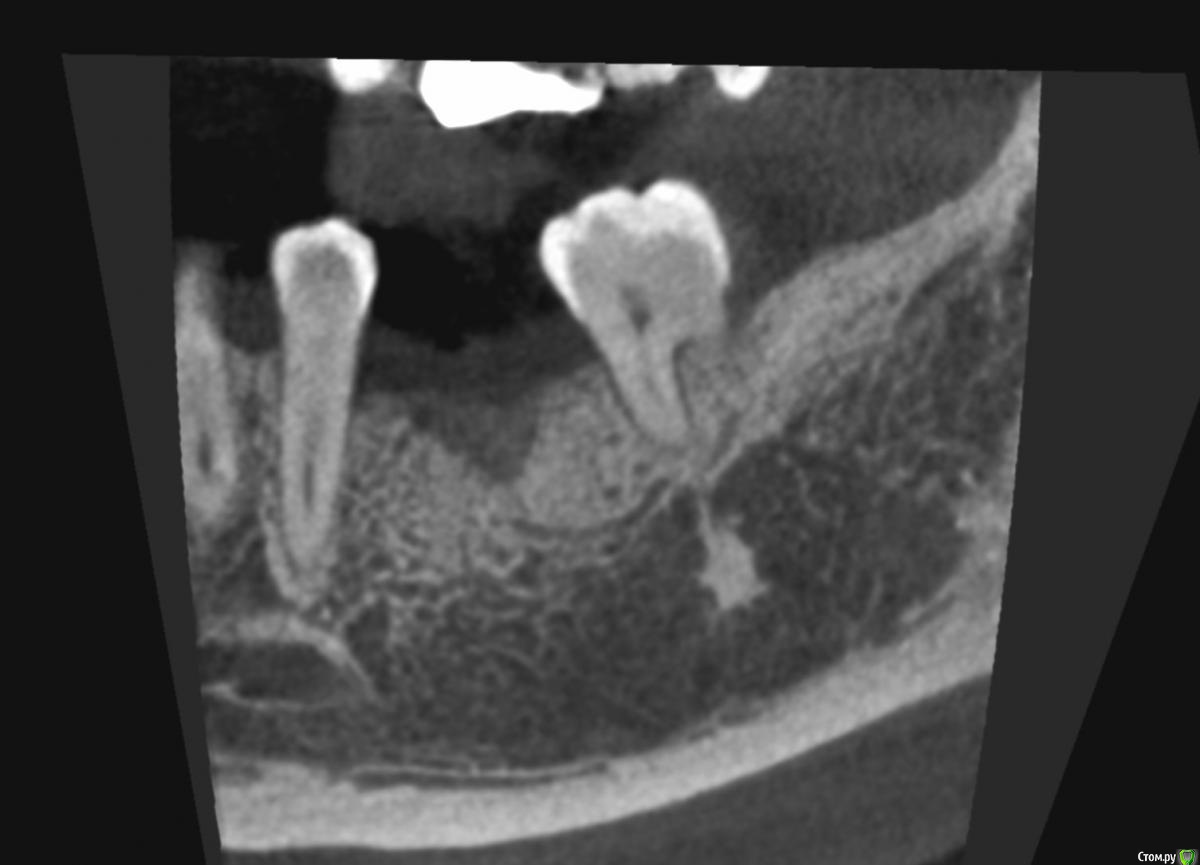

dentikl Опубликовано 20 июня, 2019 Поделиться Опубликовано 20 июня, 2019 35 удалили 26 октября 2018.Обострение гранулематозного пт.Посоветуйте плз,сейчас-1)крутить2)ждать ( сколько?)3)ревизироватьспасибо Ссылка на комментарий

Valerkaa Опубликовано 21 июня, 2019 Поделиться Опубликовано 21 июня, 2019 (изменено) dentikl, извините, что влезаю в вашу тему, не хочу создавать похожую) коллеги, посоветуйте, пожалуйста, к чему готовиться. После удаления прошло 3 месяца (удаление было вне обострения, корни в слизистой практически были). Это грануляции скорее всего? раскрыться, кюретаж и подождать? Сколько ждать по времени? Заранее спасибо. Изменено 21 июня, 2019 пользователем Valerkaa 1 Ссылка на комментарий